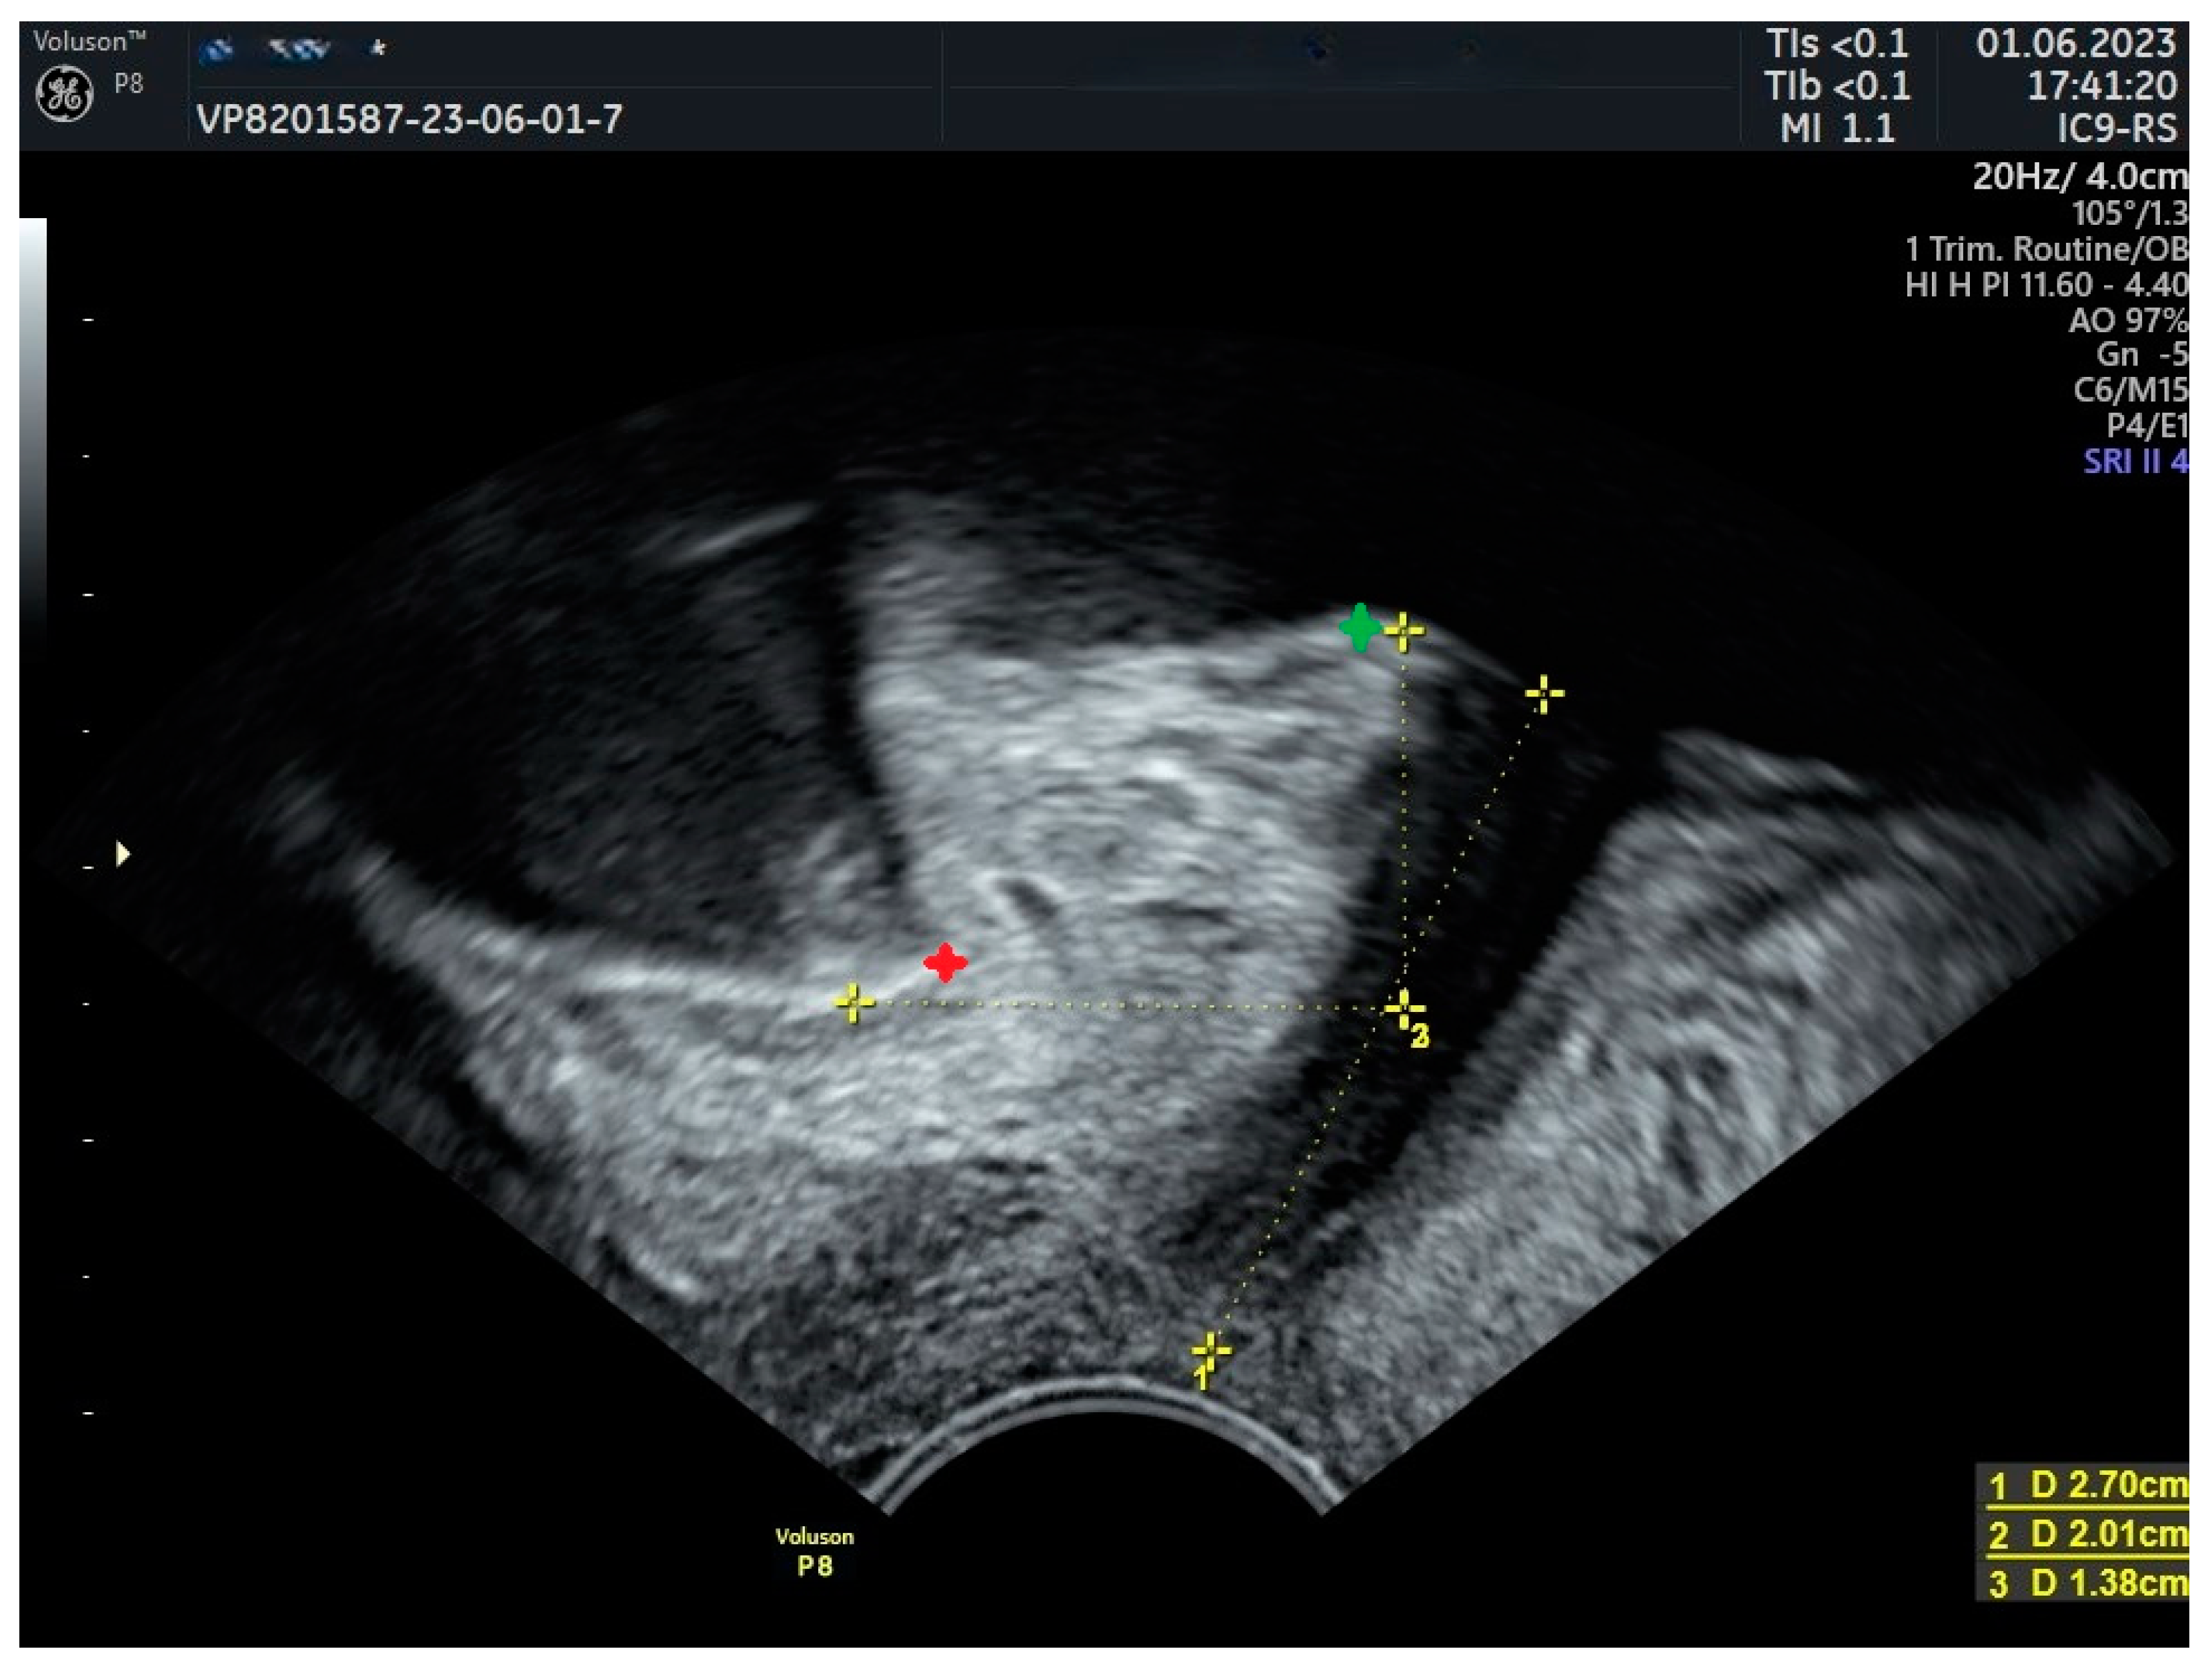

| Urinary Retention and obstructive voiding | Kociszewski et al., 2017 [35] | Median sling-LSM distance = 1.1 mm in the affected patients. |

| Reich et al., 2009 [67] | Tape-urethra distance < 2 mm in the affected patients. | |

| Viereck et al., 2013 [68] | Median sling-SLM distance = 1.5 mm. | |